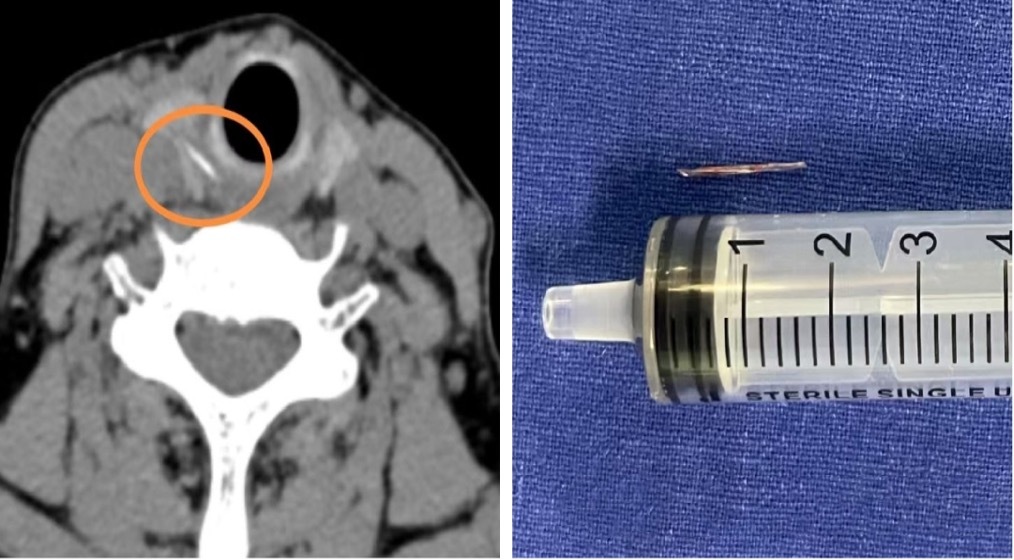

醫(yī)生從患者右側(cè)甲狀腺中,取出了一枚長(zhǎng)約1.5厘米的魚(yú)刺。上海市第十人民醫(yī)院 供圖

意識(shí)到問(wèn)題的嚴(yán)重性,李阿姨最終決定做CT,影像結(jié)果證實(shí)了之前的猜測(cè):在右側(cè)甲狀腺位置,發(fā)現(xiàn)了一條索狀的高密度異物影,這極有可能是魚(yú)刺穿透食道壁,扎進(jìn)了甲狀腺。這種情況比較復(fù)雜,僅依靠?jī)?nèi)窺鏡做微創(chuàng)手術(shù),無(wú)法取出這根‘逃逸’的魚(yú)刺,經(jīng)過(guò)審慎評(píng)估,醫(yī)療團(tuán)隊(duì)決定為李阿姨實(shí)施?全麻下頸側(cè)切開(kāi)術(shù)?。

手術(shù)中,醫(yī)生小心翼翼地探入患者頸部,精細(xì)地分離組織,完好地保護(hù)其甲狀腺、甲狀旁腺以及喉返神經(jīng),最終成功從患者右側(cè)甲狀腺中取出了一枚長(zhǎng)約1.5厘米的魚(yú)刺。探查還發(fā)現(xiàn),患者周?chē)氖车鲤つび休p度腫脹,遂對(duì)創(chuàng)面作了消毒處理。術(shù)后,李阿姨喉嚨疼痛明顯減輕,經(jīng)過(guò)抗炎治療,頸部的切口愈合良好。